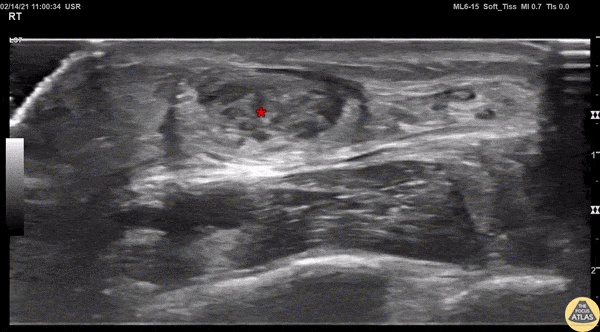

A 20s M presented with an ankle injury after landing a skateboard trick and feeling a painful pop in his posterior ankle. He had a positive Thompson test on exam. POCUS of the affected Achilles tendon was performed. This clip shows a short axis view of the Achilles tendon using the linear transducer. There is a relatively hypoechoic area (*) within the normally hyperechoic tendon, indicating focal injury to the tendon. Orthopedics was consulted, and the patient was placed into a short leg splint in plantar flexion and discharged with outpatient follow up. MRI later confirmed a focal full thickness Achilles tendon tear and the patient was scheduled for surgery. Jaimie Trenney, PA-C Denver Heath Medical Center